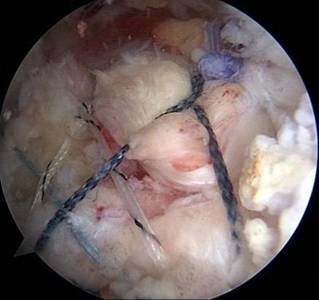

关节镜下肩袖损伤修复术治疗肩袖损伤

优点:损伤小、恢复快。

另外,微创成为我院关节科的一大亮点,膝关节周围截骨术,单髁置换术都是微创手术,患者创伤小,恢复快。我院关节科采用直接前路微创髋关节置换术,切口小,只有8-10cm,顺肌间隙进入,不切断任何肌肉,出血少,无痛,关节脱位率低,术后康复快。关节镜下微创肩袖撕裂修补,冻结肩松解,肩关节撞击症肩峰下减压术,膝关节交叉韧带损伤修补等手术,避免大切口、大创伤、恢复快。